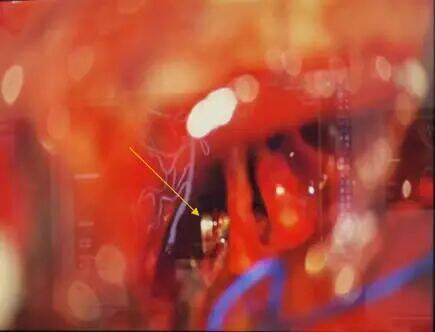

这一手术入路堪称神经外科手术的“高难度赛道”:手术区域深窄,视野暴露受限,术中操作空间极小,稍有不慎就可能损伤面听神经引发面瘫、听力障碍,或触碰脑干导致呼吸循环紊乱,手术风险极高。为确保手术万无一失,团队术前反复研读影像学资料(图1),并急诊先由主治医师张晓东、徐坤和耿仁强行脑血管造影(图2),依托神经介入指引精准标记出动脉瘤的位置、大小及与周边组织的毗邻关系;争分夺秒完善相关准备工作后行开颅动脉瘤夹闭术,术中在高倍手术显微镜下,以毫米级精度仔细分离蛛网膜粘连,小心避开神经血管“禁区”,精准选择适配的动脉瘤夹,成功将动脉瘤颈完全夹闭(图3术中动脉瘤夹位置)。术后复查头颅CT(图4)显示,动脉瘤夹位置精准,动脉瘤无残留显影,周围血管神经未受任何损伤。

术中显微镜下操作影像显示,黄色箭头所指为已夹闭动脉瘤的动脉瘤夹;